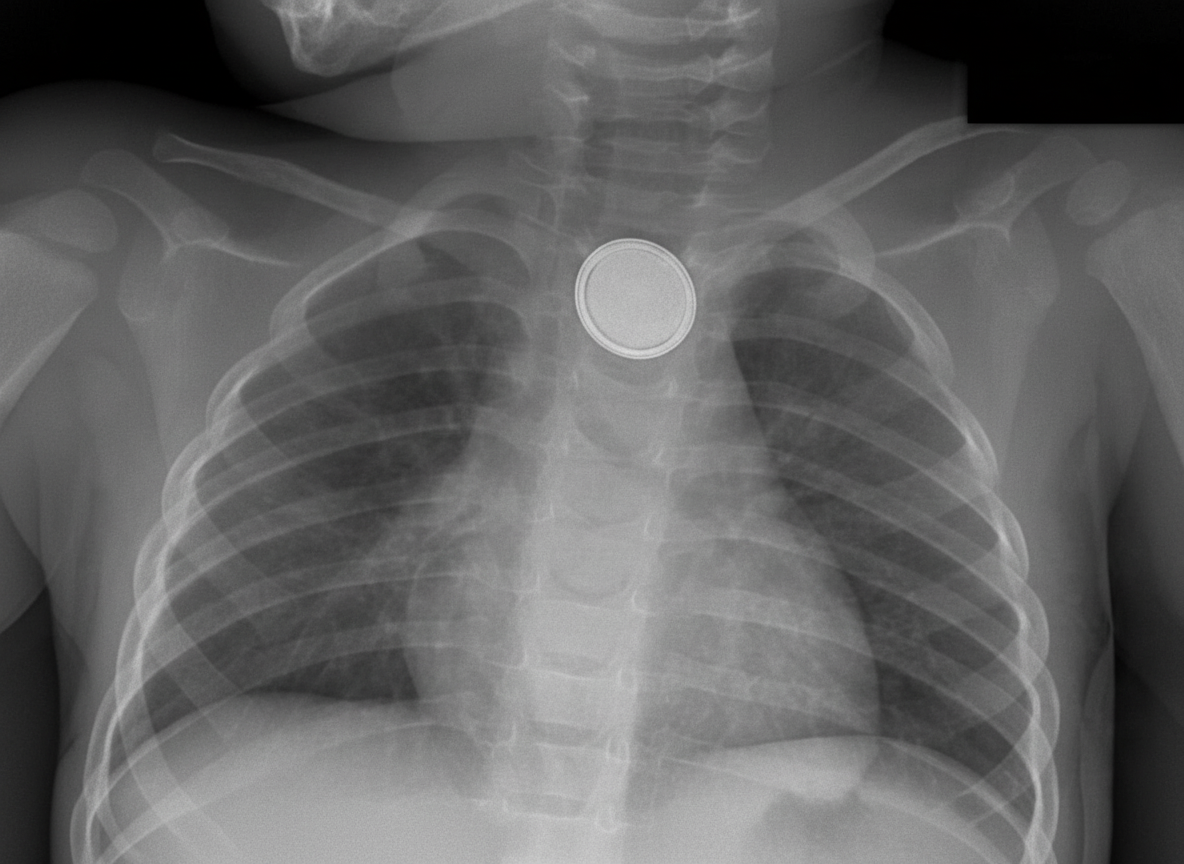

A 4-year-old child presents with findings on a chest X-ray. What is the probable location of the foreign body visible on the skiagram?

Explanation: ***Esophagus*** - Foreign bodies in the **esophagus** appear **face-on** (en face) on **anteroposterior (AP) chest X-ray**, showing the full circular outline of objects like coins. - The esophagus is the **most common location** for foreign body impaction in children, especially at anatomical narrowings like the **cricopharyngeal area**. *Trachea* - Foreign bodies in the **trachea** appear **edge-on** (sagittal view) on **AP chest X-ray**, showing only the thin edge of circular objects. - Tracheal foreign bodies typically cause **immediate respiratory distress** and **stridor**, which would be the predominant clinical presentation. *Vallecula* - The **vallecula** is located in the **oropharynx** and would not be visible on a **chest X-ray**. - Foreign bodies here typically cause **drooling**, **difficulty swallowing**, and would require **lateral neck X-ray** for visualization. *Right main bronchus* - While the **right main bronchus** is indeed the most common site for **aspirated foreign bodies** due to its **wider diameter** and **more vertical orientation**. - Bronchial foreign bodies often appear as **radiolucent objects** and may cause **unilateral hyperinflation** or **atelectasis** rather than being directly visible.